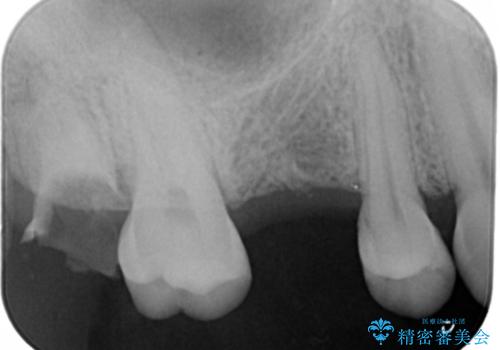

- 右上6番の歯の欠損部の治療を希望され来院された患者様です。

インプラント治療を希望されたので、インプラントとセラミッククラウンでの治療を計画しました。